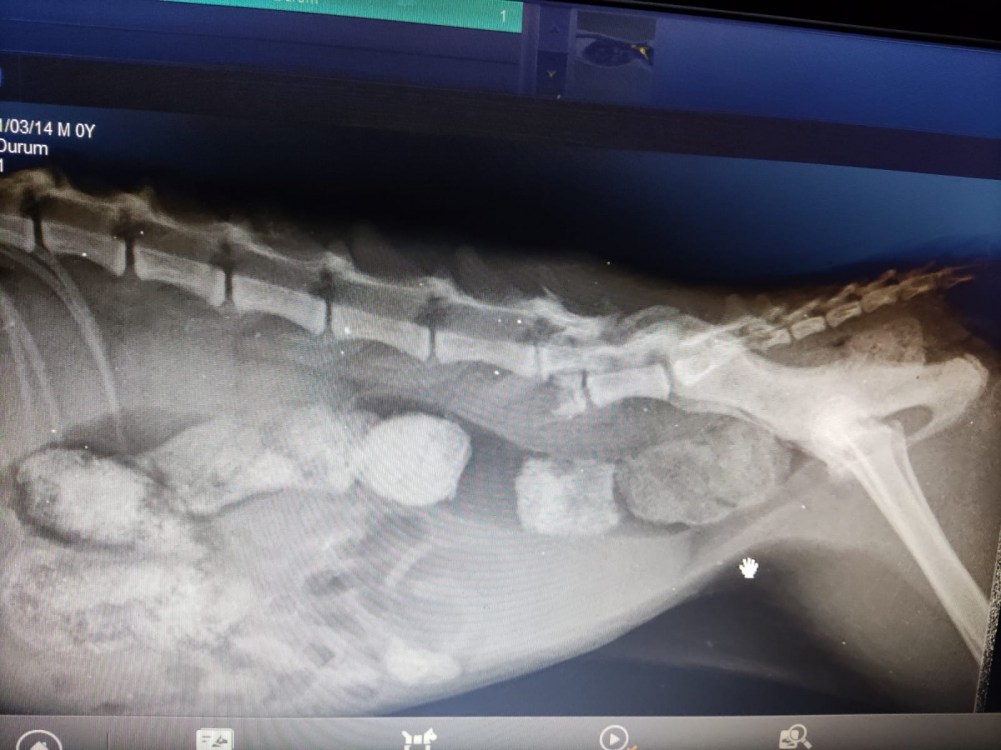

Veteriner kliniğinde yapılan muayenede BONCUK’un omuriliğinde ve arkada sağ ayağında kırık olduğu tespit edildi. Ayrıca kedinin Rektum’unda ve bağırsaklarında 4-5 santimlik genişleme olduğu, bu oluşumun kedinin tecavüze uğraması sonrası oluştuğu belirlendi.

Kedinin ilk müdahalesini yapan veteriner hekim Neslihan Yazıcı “Akşam saat 18.00 sularında hayvan sever olan hanımefendi sokakta bulduğu ve yürüyemiyor şikayeti ile kediyi kliniğimize getirdi. İlk etaptaki muayenesinde rektum bölgesinde ki 4-5 santimetrelik açıklık dikkatimizi çekti. Daha sonrasında yaz mevsiminde olduğumuz için kurtlanma durumu vardı. İlk muayenede kurtlar temizlendi. Rektum boşaltıldı. Daha sonrasında röntgen çektiğimizde omurga kırığı ve bacakta kırık olduğunu tespit ettik. Rektum da ki bu kadar büyük bir açıklık maalesef ne trafik kazası, ne şiddetten kaynaklı olmayıp direk olarak tecavüz vakası olduğunu belirttik. İlk muayeneler bu şekilde” dedi.